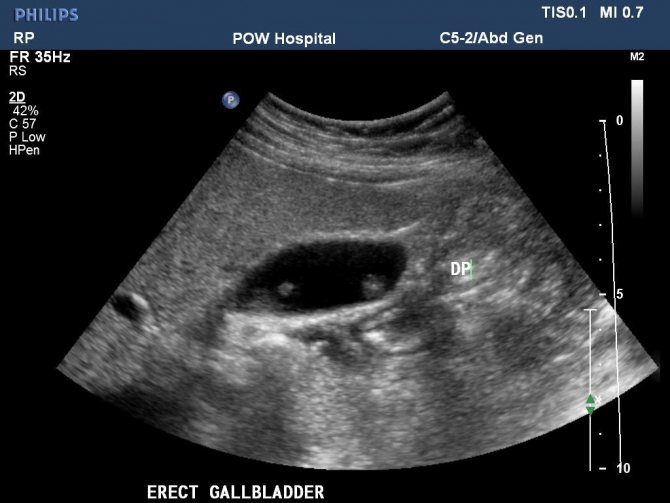

- Ультразвуковое обследование (УЗИ) органов желудочно-кишечного тракта;

- Магнитно-резонансная или компьютерная томография, если УЗИ не дает полной картины;